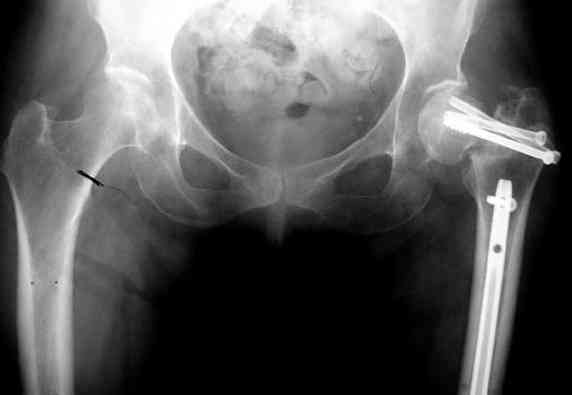

На снимках ложный сустав шейки бедра, несостоятельность фиксации. По положению шурупа можно предсказать ложный сустав, например, если screw backup за кортикальный слой около 15-20 мм, и также изменение угла от первоначального.

№4 результат на КТ